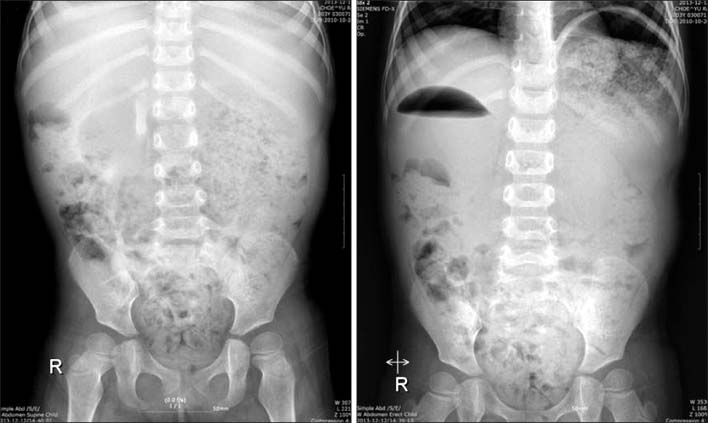

Fig. 3

(A) We found transition zone grossly. (B) We did enterotomy at the 1st portion. Duodenal web was visible and 8 Fr foley catheter was inserted via web opening. (C) We did duodenoduodenostomy.

Fig. 3 (A) We found transition zone grossly. (B) We did enterotomy at the 1st portion. Duodenal web was visible and 8 Fr foley catheter was inserted via web opening. (C) We did duodenoduodenostomy.